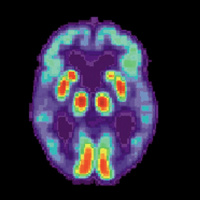

• Mapping the Brain

02/03/2016 Duration: 12min

Through the groundbreaking Human Connectome Project, researchers like Deanna Barch have spent years mapping the complex wiring of the human brain. Barch, who chairs the Department of Psychological and Brain Sciences at Washington University in St. Louis, provides a behind-the-scenes look into the project and helps us understand the links between brain connectivity and human behavior.

• Understanding Alzheimer's

17/02/2016 Duration: 11min

According to the National Institute on Aging, experts estimate that more than five million people in the United States have Alzheimer's disease, a condition that damages memory and cognitive function. David Holtzman - professor and chair of the neurology department at the Washington University School of Medicine, and associate director of the Charles F. and Joanne Knight Alzheimer's Disease Research Center - explains what is happening in the brain of someone with Alzheimer's. He also describes his own laboratory's research into the disease and shares why he believes that it should be treatable. A version of this podcast was first released in our 2012 series on Memory.